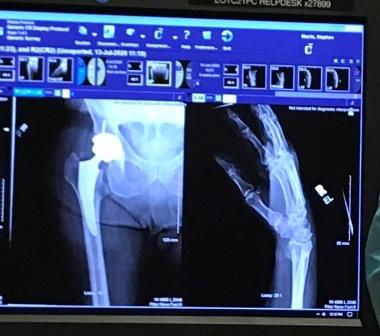

Jeff and Maggie welcomed me home after I was released from the hospital recovering from a broken wrist and hip. I learned my lesson to avoid climbing ladders. The x-rays show the damage and hardware to fix both hips. I broke the left hip in 2004 after crashing into a ski lift.